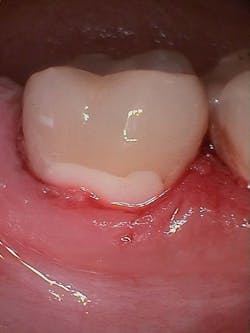

Figure 3 shows the final restoration immediately after placement. Figure 4 shows the final restoration of an initial caries lesion on the buccal. The clinician anticipated maturation of the glass-hybrid in choosing a lighter shade of A2, which initially appeared much too light. A slightly darker shade may have been more appropriate.